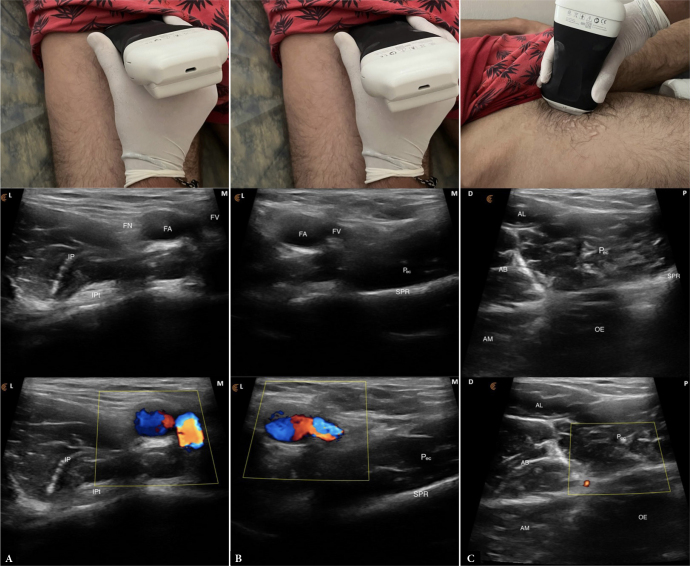

Orphan muscle of groin pain: ultrasound imaging of the pectineus muscle.

腹股沟疼痛孤儿肌:耻骨肌的超声成像。